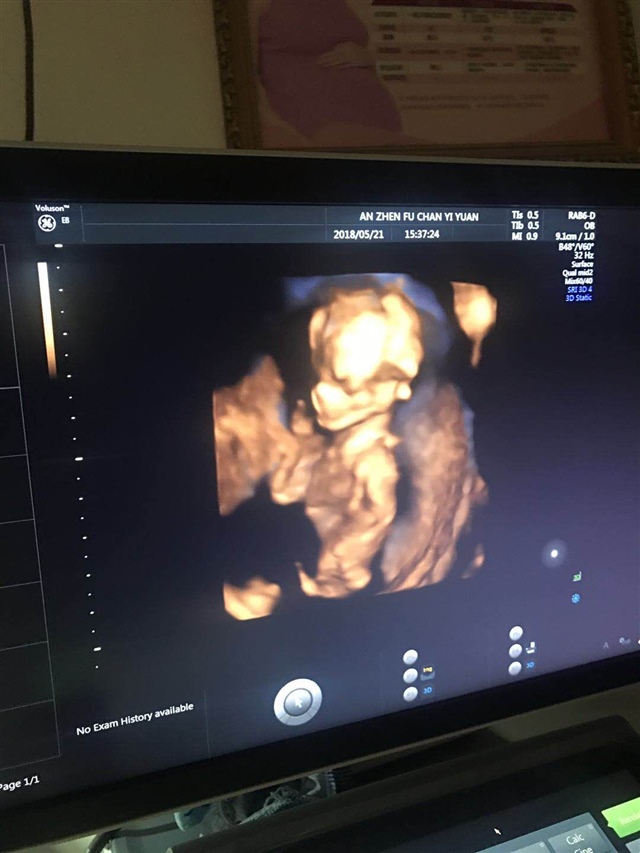

孕29周+1天

男孩